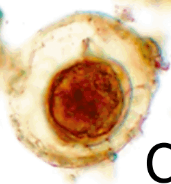

What is this the egg for?

Taenia